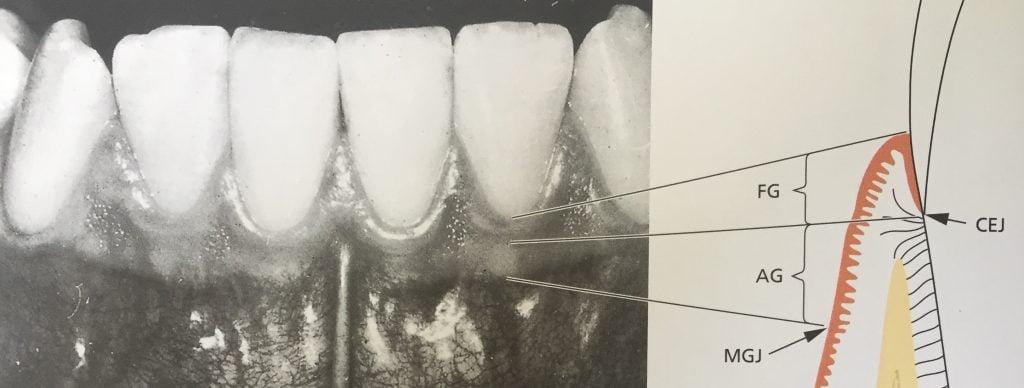

A gengiva cobre o processo alveolar e circunda a porção cervical dos dentes. Assume a sua forma e textura definitiva em associação com a erupção dos dentes e consiste em uma camada epitelial e tecido conjuntivo adjacente, chamado de lâmina própria.

É dividida anatomicamente em marginal (livre), inserida e área interdental (interproximal, papila interdental).

FG: Gengiva Livre

AG: Gengiva Inserida

MGJ: Junção Muco Gengival

CEJ: Junção Cemento-Esmalte

(Fonte: LINDHE, 2010)

A gengiva inserida se apresenta firme, resiliente e fortemente aderida ao periósteo do osso alveolar adjacente. A altura da faixa da gengiva inserida é a distância entre a junção muco gengival e a projeção externa do fundo do sulco gengival ou da bolsa periodontal.